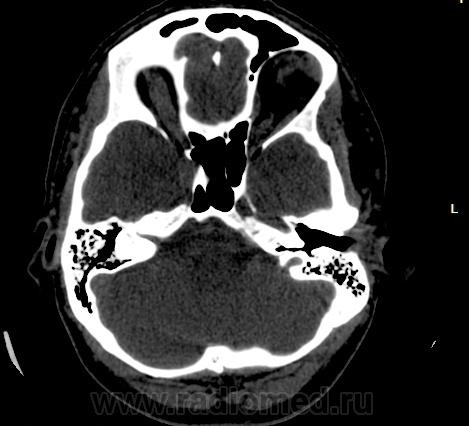

Прошу разрешить спор. По КТ - норма. Женщина, 1967г.р., жалобы на головную боль, больше в затылочной области. По-моему, не КТ-шное это дело но всеж...

Открыл. В мозгу ничего осбенного не увидел. По поводу Киари ничего не скажу, на аксиалах не вижу, а реконструкции эти срезы не строят Да и отношусь я к этой патологиии как к норме.

Аномалию Арнольда-Киари 1типа.

На МРТ выставили  аномалию Арнольда-Киари 1, нам сказали фу... На что я ответил, что по " ловцу и рыба". Во - первых, линию на КТ провести сложно ( в данном иссл.), во-вторых - естественные артефакты костей основания. И вообще пошли на...МРТ! Но осадок остался.

Для Арнольда-Киари I МРТ - как раз и есть метод диагностики, а на КТ это дело можно лишь заподозрить. Плюньте на осадок. Ну хотите, я плюну?) Тока отойдите, а то разъест))).